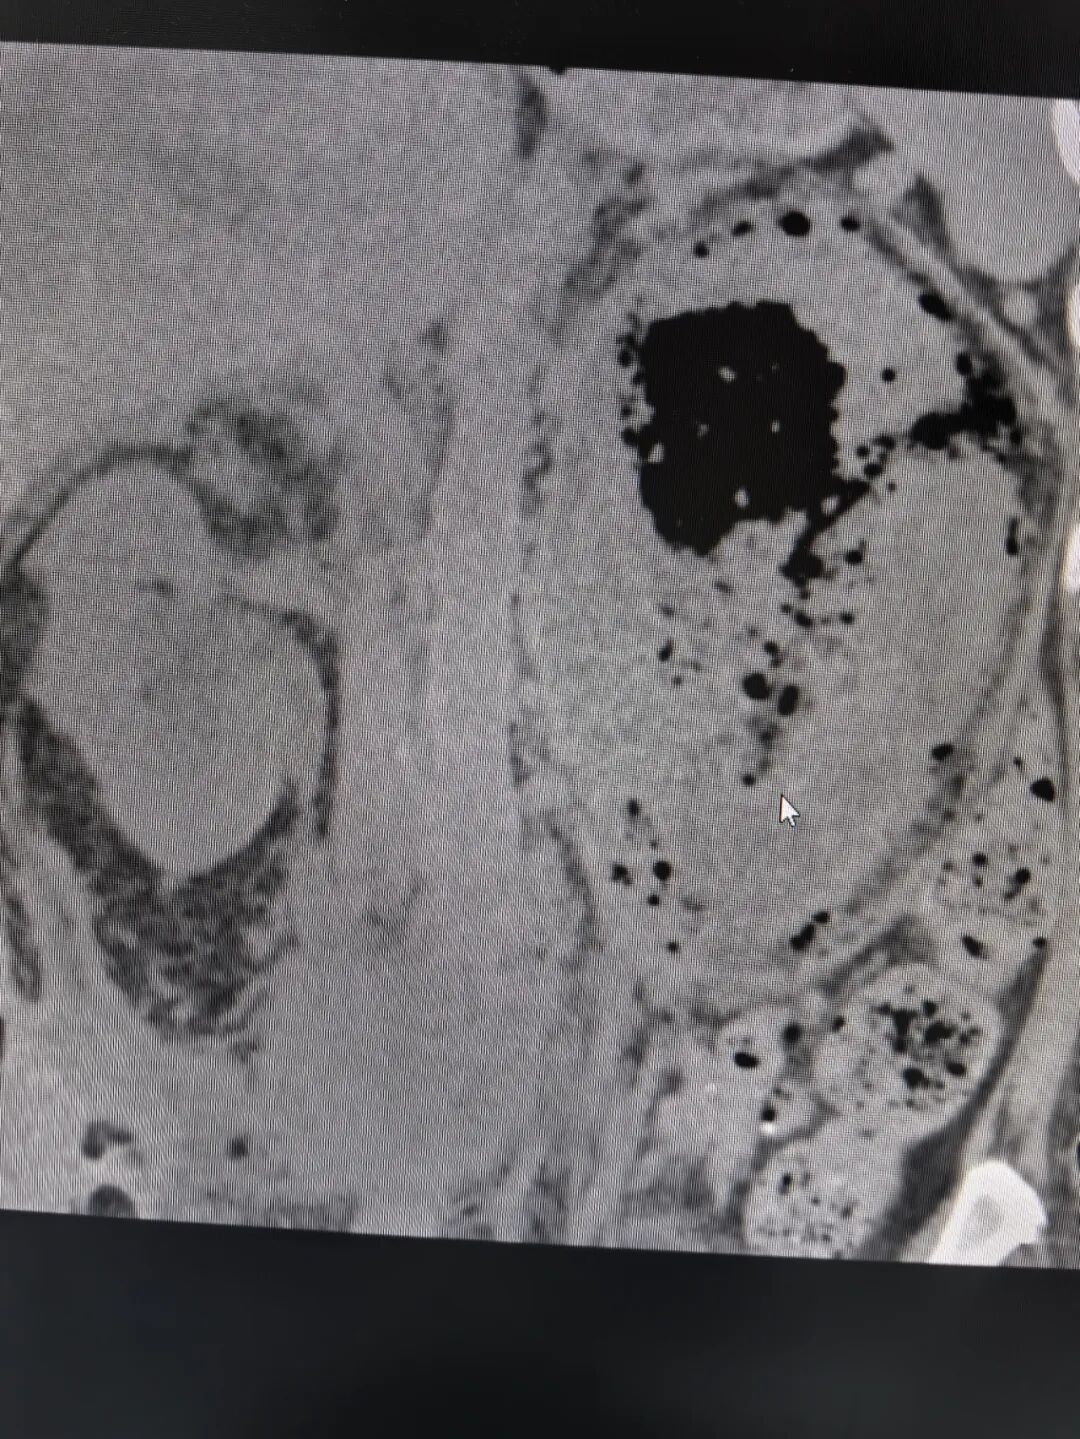

谢庆祥教授接诊后,对患者进行了全面而详细的检查。患者腹部CT见左肾积气严重、左肾大部分毁损、左肾盂内可疑内容物、右肾盂积水、腹膜后炎性积液致双侧输尿管腹段粘连、压迫。此外,患者还有双侧胸腔积液、肺部感染、肾功能不全、糖尿病、重度贫血、低蛋白等病症。进一步完善双肾CT增强检查,提示左肾多处脓肿伴积气,左肾实质毁损严重,左肾增强显影不理想。